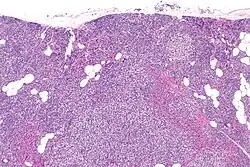

Primary hyperplasia of the parathyroid gland, results from both hypocalcaemia and increased phosphate levels by decreasing expression of calcium sensing receptors and vitamin D receptors at the parathyroid gland.[8][4] These decreases in receptor expression lead to hyperfunctioning of the parathyroid. Hyperfunction of the parathyroid gland is thought to exacerbate primary hyperplasia which evolves further to a secondary more aggressive hyperplasia. Histologically, these hyperplasic glands can be either diffuse or nodular.[24] Primary hyperplasia, usually resulting in diffuse polyclonal growth is manly related to reversible secondary hyperparathyroidism. Secondary hyperplasia of the parathyroid gland is more often a nodular, monoclonal growth that sustains secondary hyperparathyroidism and is the catalyst in the progression to tertiary hyperparathyroidism. Nodular hyperplastic glands in tertiary hyperparathyroidism are distinctly larger in both absolute size and weight up to 20-40-fold increases have been reported.[25][26][24]

Parathyroid glands are normally composed of chief cells, adipocytes and scattered oxyphil cells.[27][14] Chief cells are thought to be responsible for the production, storage and secretion of parathyroid hormone. These cells appear light and dark with a prominent Golgi body and endoplasmic reticulum. In electron micrographs, secretory vesicles can be seen in and around the Golgi and at the cell membrane. These cells also contain prominent cytoplasmic adipose.[27][14] Upon onset of hyperplasia these cells are described as having a nodular pattern with enlargement of protein synthesis machinery such as the endoplasmic reticulum and Golgi. Increased secretory vesicles are seen and decreased intercellular fat is characteristic.[27][24] Oxyphil cells also appear hyperplasic however, these cells are much less prominent.

Hyperparathyroidism, in general, is caused by either tumorous growth in one or more parathyroid glands or a prolonged decrease in blood calcium levels or hypocalcaemia which in turn stimulates the production of parathyroid hormone release from the parathyroid gland.[10][11] The parathyroid gland is located beside the thyroid gland in the neck, below and in front of the larynx and above the trachea. It is composed of four glands in total that monitor blood calcium levels via the calcium sensing receptors, a g-coupled protein receptor.[12] The parathyroid glands main role is calcium homeostasis.[13][12] Histologically, these glands are composed of chief cells and oxyphil cells with the chief cell primarily responsible for the storing and release of parathyroid hormone. These cells are arranged in a pseudo-follicular pattern similar to the thyroid follicles. Keratin staining is used to image the parathyroid hormone granules.[9][14]